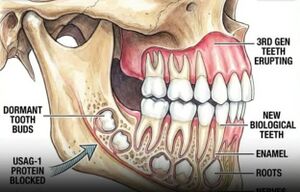

في مارس 2021، تمخضت دراسة جديدة أجراها علماء من جامعتي كيوتو وفوكوئي عن أن جسماً مضاداً للجين USAG-1 قادر على تحفيز نمو الأسنان لدى الفئران التي تعاني من انعدام الأسنان الخلقي. وقد نُشرت هذه الدراسة في مجلة ساينس أدڤانسز. على الرغم من أن فم الشخص البالغ الطبيعي يحتوي على 32 سناً، إلا أن حوالي 1% من السكان لديهم عدد أسنان زائد أو ناقص نتيجة لحالات خلقية. وقد بحث العلماء في الأسباب الجينية لحالات امتلاك عدد كبير من الأسنان، بحثاً عن أدلة تساعد في إعادة توليد الأسنان لدى البالغين. وبحسب كاتسو تاكاهاشي، أحد المؤلفين الرئيسيين للدراسة ومحاضر أول في كلية الطب بجامعة كيوتو، فقد تم بالفعل تحديد الجزيئات الأساسية المسؤولة عن نمو الأسنان. يقول تاكاهاشي: "إن عملية تكوين الأسنان الفردية تعتمد على تفاعلات العديد من الجزيئات بما في ذلك پروتين تشكل العظام (BMP)، وتأشير الپروتين Wnt. لا تقتصر وظيفة پروتينات BMP وWnt على نمو الأسنان فحسب، بل إنها تنظم نمو العديد من الأعضاء والأنسجة حتى قبل أن يصل حجم جسم الإنسان إلى حجم حبة الزبيب. ولذلك، يُتجنب عادةً تناول الأدوية التي تؤثر بشكل مباشر على نشاطها، لأن آثارها الجانبية قد تؤثر على الجسم بأكمله. انطلاقاً من التخمين بأن استهداف العوامل التي تعارض BMP و Wnt على وجه التحديد في نمو الأسنان قد يكون أكثر أماناً، فقد نظر الفريق في الجين USAG-1.[5]

يزيل الدواء التجريبي (وهو جسم مضاد يثبط عمل الجين USAG-1)، مما يحفز براعم الأسنان الخاملة على النمو. في التجارب، استعاد 68% من المشاركين الذين تتراوح أعمارهم بين 30 و70 عاماً سناً واحداً على الأقل كاملاً بجذوره وميناه، واندماجه الطبيعي مع عظم الفك. تعمل الأسنان التي استعادت نموها تماماً مثل الأسنان الأصلية، دون أي اختلاف عن تلك التي يولد بها البشر. يتضمن العلاج حقناً شهرية لمدة ستة أشهر، ثم يبزغ السن بشكل طبيعي مثل أسنان الطفولة.[6]

فئران تعاني من نقص الجين USAG-1، مما أدى إلى بقاء القواطع اللبنية الضئيلة ونموها كأسنان زائدة.

صورة توضح دور الجين USAG-1 في كبت إعادة نمو الأسنان.